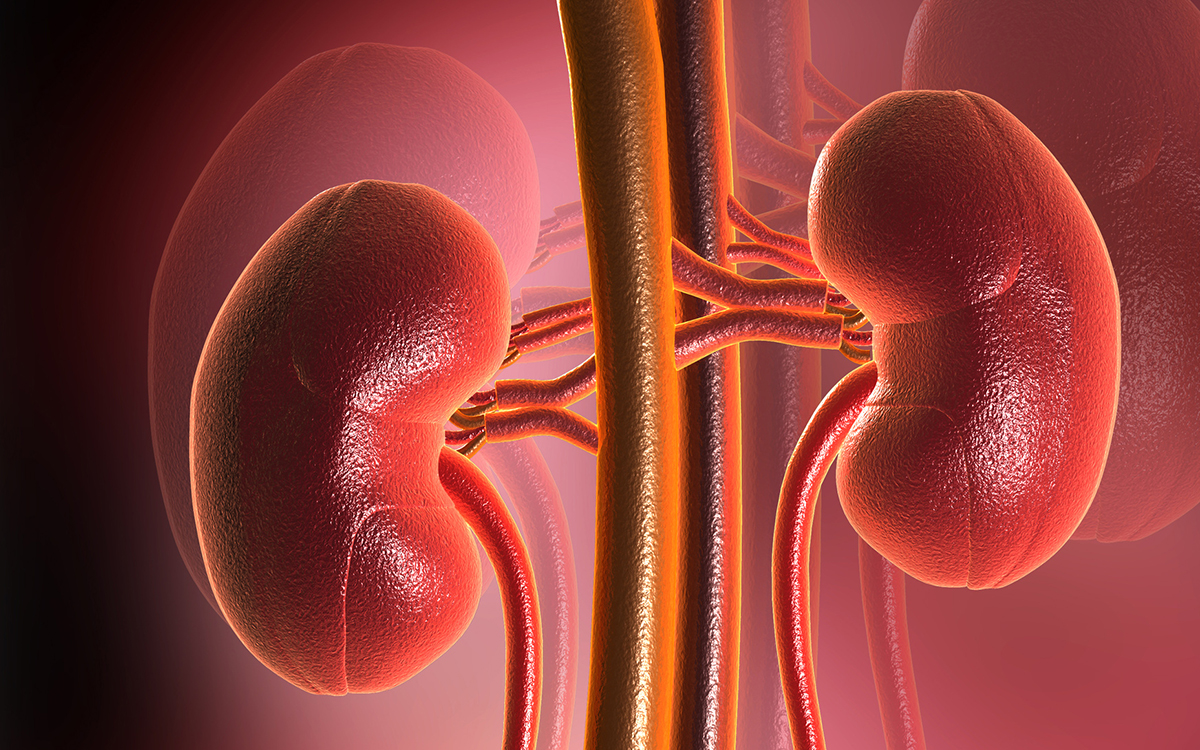

Строение почек человека: Фото и описание

Раздел: Ракурсы мышления